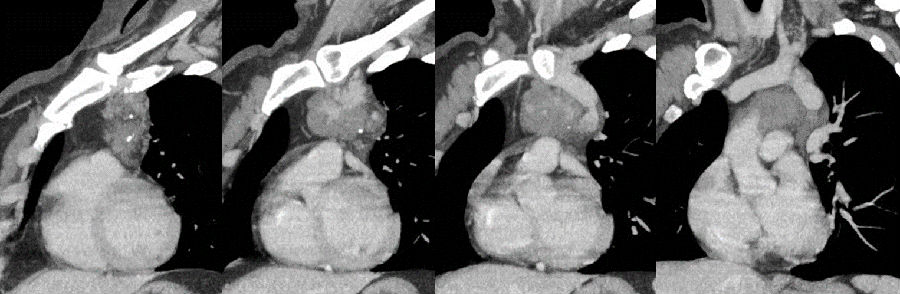

病例提供 伍建林教授(大连大学附属中山医院) 简要病史 患者,女,45岁 主诉:胸前区疼痛、胸闷3年,加重半月余。 现病史:3年前患者无明显诱因出现间断性胸前区疼痛、胸闷,伴后背部疼痛,运动后上述症状加重,无呼吸困难,无头晕、头痛,于当地医院行冠脉造影示:冠状动脉粥样硬化,具体治疗不详,出院后自服硝酸甘油,上诉症状可缓解。半月前,患者上诉症状加重,于当地医院行胸部CT检查发现:左前上纵隔肿物,并于我院门诊以“纵隔肿物”收入院进一步诊治。病来无咀嚼无力,无气短,无咯血,无关节疼痛,无进行性消瘦,无恶心、呕吐、低热盗汗等。 既往史:胸背部脂肪瘤术后8年;高血压病史4年,自服药物治疗效果良好;否认其他病史。 一般查体与专科查体无明显异常。 影像资料